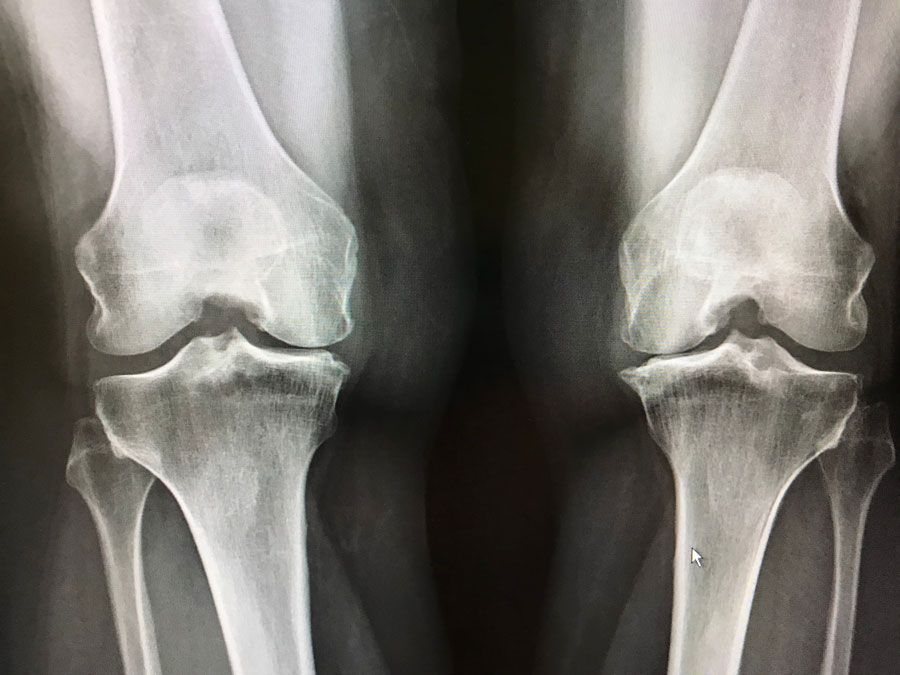

Pérdida de peso inducida por medicamentos contra la obesidad y mortalidad por todas las causas en pacientes con osteoartritis de rodilla o cadera

07 diciembre 2023

En este estudio poblacional, una tasa de pérdida de peso lenta a moderada, pero no rápida, inducida por medicamentos contra la obesidad se asocia con un menor riesgo de mortalidad por todas las causas en personas con sobrepeso u obesidad y artrosis de rodilla o cadera. Arthritis Rheumatol. 6 de diciembre de 2023